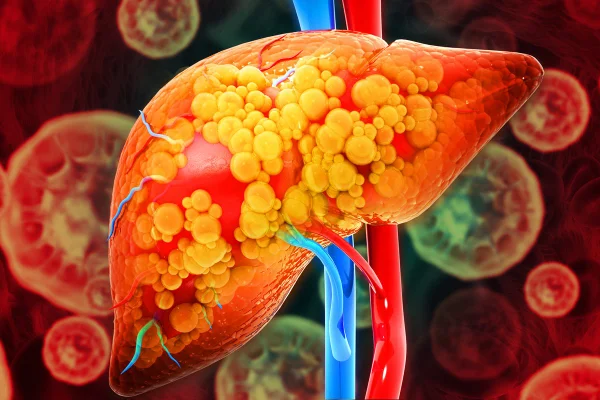

A esteatose hepática é caracterizada pelo acúmulo de gordura no fígado superior a 5% do volume do órgão e que, ao longo do tempo, prejudica o funcionamento do organismo. As origens do quadro e os riscos que ele traz têm despertado cada vez mais interesse da população.

Até poucos anos atrás, acreditava-se que só um tipo de esteatose hepática era verdadeiramente preocupante: o associado ao uso de álcool. Entretanto, descobriu-se que mesmo pessoas abstêmias, se tiverem um regime dietético desregulado e não praticarem atividades físicas, podem desenvolver a doença hepática esteatótica associada à disfunção metabólica (MASLD), nomenclatura que foi adotada a partir de 2023. O quadro, conhecido popularmente como gordura no fígado, pode até desencadear o câncer no órgão.

A esteatose hepática é popularmente conhecida como gordura no fígado

A condição de gordura no fígado acomete 30% da população mundial

O acúmulo de gordura é o primeiro passo de uma série de comprometimentos de saúde em cadeia. Quando há esteatose, o fígado pode se inflamar, e em cerca de 20% dos casos, a condição evolui para esteatohepatite (MASH), uma inflamação crônica do fígado.

A evolução dela é a fibrose, a formação de um tecido cicatricial no órgão que aumenta e muito o risco de desenvolvimento de cirrose e de câncer hepático. Entre pacientes com cirrose, o risco de câncer de fígado ao longo dos anos chega a 5% — mais de mil vezes maior que o da população geral.

O grau da doença indica extensão da gordura: leve (grau 1) acomete até 30% das células hepáticas, moderada (grau 2) atinge entre 30% e 60%, e grave (grau 3) ultrapassa 60%. Quanto maior o acúmulo, mais elevado risco de inflamação, fibrose e cirrose.